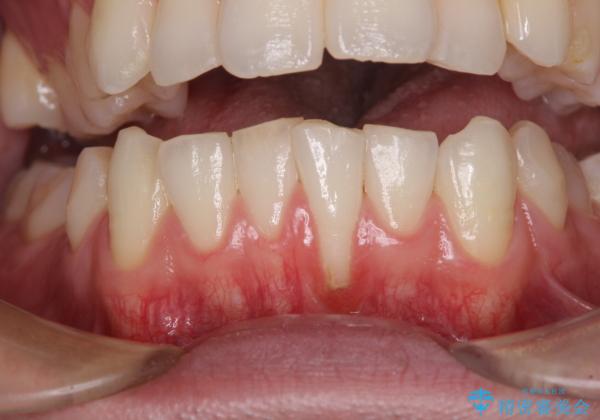

1回目の処置で多少は被覆され歯肉が厚くなりましたが、十分とは言えなかったため、2回目の処置を行いました。

2回目の処置後には十分な厚みと、十分な被覆量を獲得することができました。